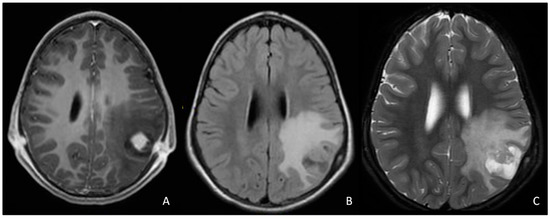

- Griffith, J.L.; Morris, S.M.; Mahdi, J.; Goyal, M.S.; Hershey, T.; Gutmann, D.H. Increased prevalence of brain tumors classified as T2 hyperintensities in neurofibromatosis 1. Neurol. Clin. Pract. 2018, 8, 283–291. [Google Scholar] [CrossRef]

- D’Amico, A.; Mazio, F.; Ugga, L.; Cuocolo, R.; Cirillo, M.; Santoro, C.; Perrotta, S.; Melis, D.; Brunetti, A. Medullary unidentified bright objects in Neurofibromatosis type 1: A case series. BMC Pediatr. 2018, 18, 91. [Google Scholar] [CrossRef]

- Griffiths, P.D.; Blaser, S.; Mukonoweshuro, W.; Armstrong, D.; Milo-Mason, G.; Cheung, S. Neurofibromatosis bright objects in children with neurofibromatosis type 1: A proliferative potential? Pediatrics 1999, 104, e49. [Google Scholar] [CrossRef] [PubMed]